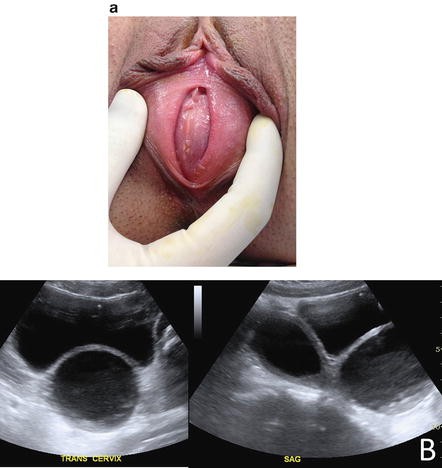

Hematocolpos On Imperforated Hymen And Acute Urinary Retention A Rare Disease About Seven Observations And Literature Reviews